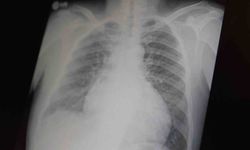

Tunceli’de kalp yetmezliği tanısı olan ve yaklaşık 3 hafta önce sağlık durumu kötüleşen İbrahim Doğan’ın, Tunceli Devlet Hastanesi Koroner Yoğun Bakım Ünitesine yatışı yapıldı. Doğan’ın mevcut kalp yetmezliğinin son dönemine girmesi, taburcu olma ihtimalinin ve kalbinin desteksiz çalışmasının mümkün olmaması ve İleri Düzey Kalp Destek Cihazına (LVAD) ihtiyacı olması sebebiyle ileri bir merkeze sevk işlemleri başlatıldı. Doğan’ın tedavisinin gerçekleştirilebileceği uygun bir merkeze naklinin en uygun ekip gözetiminde gerçekleştirilmesi amacıyla Sağlık Bakanlığı Hava Operasyon Merkezi ile görüşme yapıldı. Görüşmeler neticesinde, hastanın İstanbul Kartal Koşuyolu Yüksek İhtisas Eğitim ve Araştırma Hastanesine nakli Sağlık Bakanlığı’na ait uçak ambulans ile sağlandı.